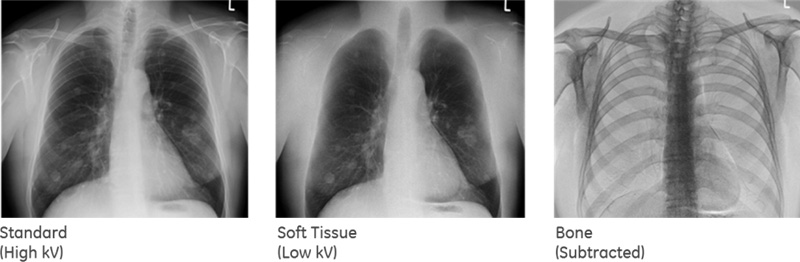

Dual Energy Subtraction

- Achiziționarea de imagini multiple la intervale foarte scurte de timp (milisecunde) cu diferite niveluri de energie;

- Procesarea imaginii ca radiografie standard sau cu evidențierea structurilor de interes;